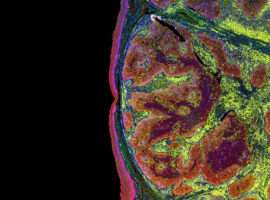

O IDOR nasceu do desejo de construir conhecimento científico sólido na área médica. Desde sua criação, vem atuando em diferentes temas, com um time multidisciplinar de pesquisadores e parcerias com grandes instituições do Brasil e do mundo. Como resultado, nossa equipe já publicou centenas de artigos em revistas científicas internacionais.

O IDOR teve papel de destaque, por exemplo, no esforço multi-institucional que estabeleceu a relação causal entre o vírus Zika e o aumento da ocorrência de microcefalia no Brasil em 2016. Ainda, foi pioneiro, na América Latina, na criação de células-tronco reprogramadas a partir da urina de pacientes, um método não invasivo.